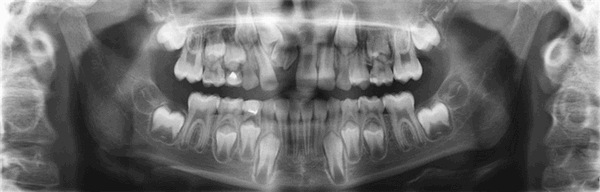

Самое распространенное из них — задержка прорезывания зубов. В этом случае особенно важно обратиться за помощью к стоматологу и провести рентгенологическое обследование, чтобы выяснить, почему постоянный зуб не прорезался. Возможные причины:

- генетическая предрасположенность

- зуб недостаточно развит и задержался в челюсти

- нет зачатка постоянного зуба

- зуб неправильно расположен в кости (ретенирован)

Сроки прорезывания постоянных зубов при правильном развитии ребенка совпадают со временем выпадения временных зубов (табл. 4).

Таблица 4. Сроки прорезывания постоянных зубов.

Прорезывание постоянных зубов начинается с первого постоянного моляра в 6 лет. Затем последовательно в возрасте 6 - 8 лет прорезываются центральные и боковые резцы. В 9 - 10 лет прорезываются первые премоляры, за которыми, чаще всего, следуют клыки (10 - 11 лет) и вторые премоляры (11 - 12 лет). В 12 - 13 лет прорезываются вторые постоянные моляры. Таким образом, к 12 - 13 годам все временные зубы заменяются постоянными. Окончательное формирование корней завершается к 15 годам.